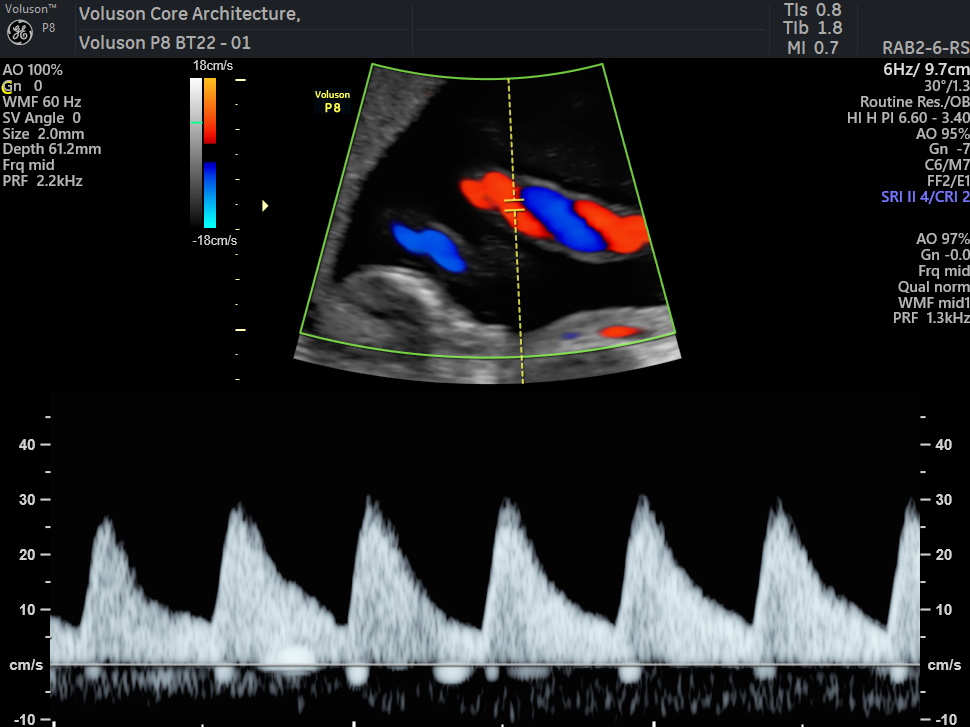

✔️ Ensures the baby is receiving enough oxygen and nutrients

✔️ Evaluates blood flow in the placenta

✔️ Checks blood supply to the baby’s brain and heart

✔️ Helps with early detection of:

Fetal growth restriction – Low oxygen levels – Fetal anemia – Effects of high blood pressure or diabetes during pregnancy